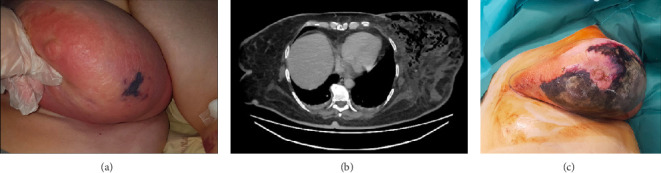

Introduction: Necrotizing fasciitis (NF) is a rapidly progressive, life-threatening soft tissue infection that primarily involves the fascia and subcutaneous tissues. While it typically affects the extremities, perineum, or trunk, NF of the breast remains an exceptionally rare and underdiagnosed entity, often leading to delayed intervention and high morbidity. Case Presentation: We report the case of a 57-year-old woman with poorly controlled Type 2 diabetes who presented to the emergency department with diabetic ketoacidosis and erythema of the left breast. Initial arterial blood gas analysis revealed profound metabolic acidosis (pH 6.89, PaCO2 12.8 mmHg, bicarbonate 2.5 mmol/L, and base excess -31.5 mmol/L). Despite initial antibiotic therapy, the breast symptoms worsened, raising concern for inflammatory breast cancer. Imaging revealed subcutaneous emphysema and extensive soft tissue inflammation. A diagnosis of NF was confirmed, prompting emergency surgical intervention. A left mastectomy was performed, with resection of necrotic fascia and pectoralis major. Microbiological cultures identified a polymicrobial infection with Escherichia coli, Citrobacter, and Actinotignum schaalii. The patient received targeted antibiotic therapy and supportive care, including pain management and fluid-electrolyte balance. Reconstruction was initiated 8 months later with contralateral breast reduction and fat grafting. Discussion: Breast NF poses significant diagnostic challenges due to the organ's unique vascular anatomy and the rarity of the condition. Delays in diagnosis can be fatal. This case underscores the importance of clinical vigilance, prompt imaging, and early surgical debridement. The synergistic effect of polymicrobial infections was evident in the rapid progression. Reconstruction remains an essential component of care, with satisfactory outcomes achievable through fat grafting and symmetry procedures. Conclusion: Breast NF requires rapid diagnosis and aggressive multidisciplinary management. This case illustrates the need for increased awareness to reduce diagnostic delays and improve survival and reconstructive outcomes.